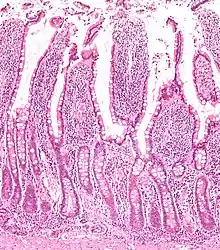

Vilosidades e criptas tingidas com H-E.

Possuem epitélio simples colunar e fazem parte da camada mucosa do intestino.